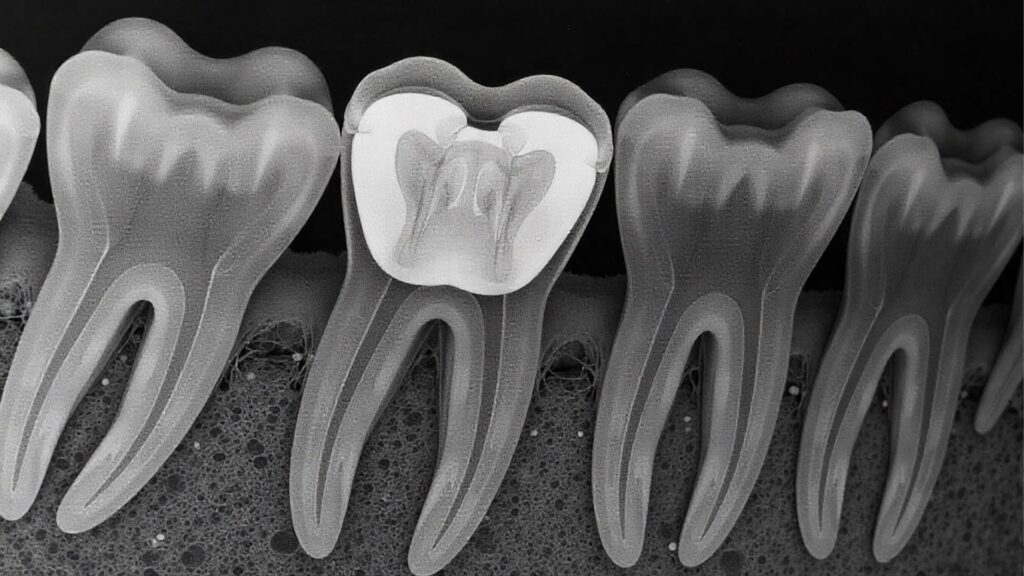

اتضح أن حشوة معدنية داخل أحد أضراسه كانت مكوّنة من خليط يسمح لها بالتصرّف مثل “هوائي بسيط”، قادر على التقاط ترددات معينة من موجات الراديو. وعندما تتزامن هذه الترددات مع وضعية معينة للفك أو الجمجمة، فإن العصب السمعي يترجمها على شكل صوت داخلي.

نعم. ورغم ندرتها الشديدة، فإن ظاهرة سماع موجات راديو من خلال الأسنان أو الحشوات المعدنية تم تسجيلها مرات قليلة خلال العقود الماضية.

في دراسة نشرتها مجلة British Dental Journal، أشار الباحثون إلى حالات مشابهة رُصدت منذ الحرب العالمية الثانية، عندما كان بعض الجنود يسمعون أصواتًا لاسلكية بسبب حشوات معدنية بدائية الصنع.